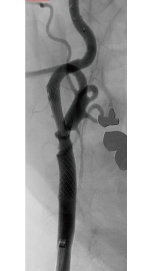

頚動脈狭窄症

食生活の欧米化や動脈硬化性リスク因子の増加などにより、頚動脈狭窄症の患者さんが飛躍的に増加しております。当院は頚動脈狭窄症の治療を本邦で最も多く扱う施設の一つであり、現在までに、頚動脈プラーク性状に基づく治療方針決定、薬剤によるプラーク安定化などの研究を行ってきました。

近年では、頚動脈狭窄症における長期転帰に関する研究なども高い評価を受けております。